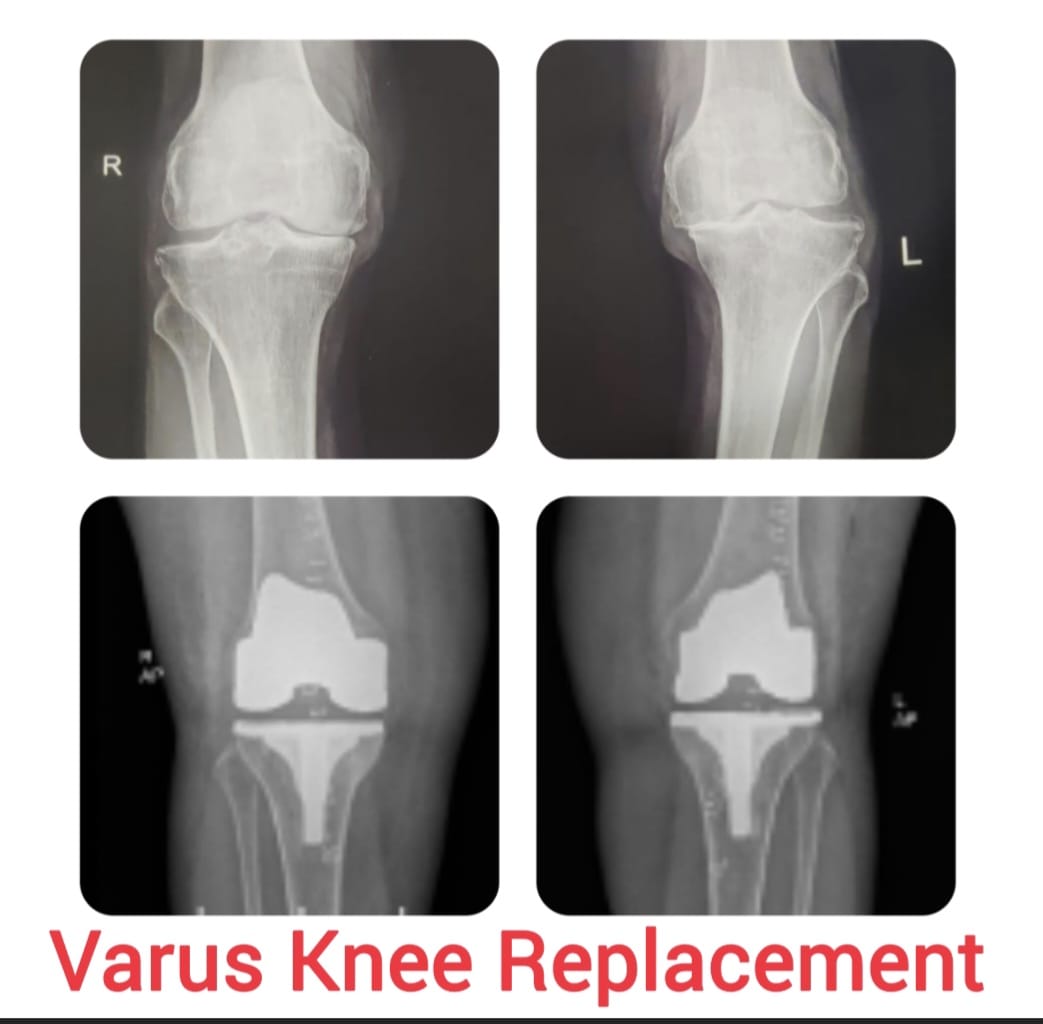

Knee replacement, also known as knee arthroplasty, is a surgical procedure performed to relieve chronic knee pain and restore joint function in patients suffering from advanced arthritis, severe joint damage, or deformities. The procedure involves replacing damaged cartilage and bone surfaces with durable artificial implants that restore smooth knee movement.

Knee arthroplasty is carefully planned based on the patient’s age, activity level, degree of joint damage, and overall health. Modern surgical techniques and advanced implant designs allow improved alignment, stability, and long-lasting outcomes with reduced postoperative discomfort.